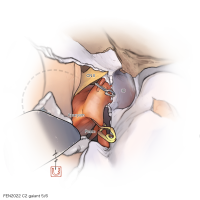

FEN2022シリーズ